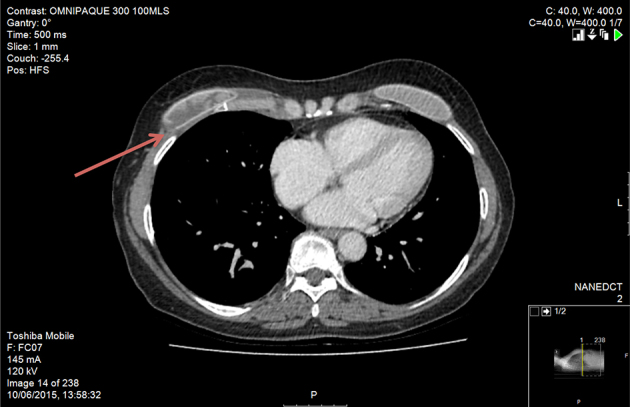

The patient underwent ultrasonography guided biopsy of the right neck because of the proximity of the lymph node to the neck vessels. The ultrasonography (Fig 1) showed a 1.3cm lesion with acoustic shadowing giving the impression of possible calcinosis but the nature of the lesion could not be discerned fully. Fine needle aspiration was equally inconclusive, showing multinucleated giant cells with foamy cytoplasm, and it could not rule out malignancy. The patient then underwent computed tomography (CT) of the neck and chest (Fig 2), which revealed an enlarged supraclavicular node that looked benign. Bilateral breast implants were also noted.

Figure 2.

Axial computed tomography of the neck showing enlarged right-sided supraclavicular lymph node (arrow), benign in appearance